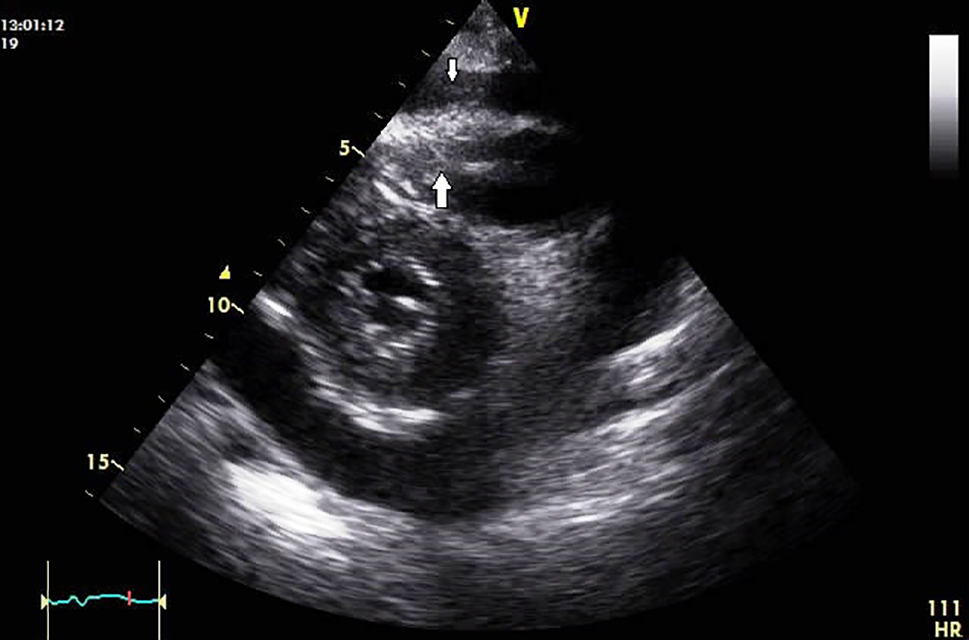

Pericardial effusions are difficult to diagnose, as the clinical examination might be essentially normal in haemodynamically stable patients and tachycardia may be the only sign [1,2]. Cardiomegaly with a flask-shaped heart and clear lung fields on chest X-ray is suggestive of significant pericardial effusion [1,8,10]. ECG may be normal or may show non-specific ST and T-wave abnormalities. Occasionally, low QRS voltage may be seen, but that is more specific for tamponade [1]. Two-dimensional transthoracic echocardiography is the preferred investigation for pericardial effusion as it can determine the size, location, and haemodynamic significance of a pericardial effusion and is also low cost and easily available [1,2,4,13,14]. Upon detection of the effusion, it is imperative to assess the size of the effusion, look for signs of tamponade and any evidence of associated illness [2]. Though echocardiography is fairly conclusive in diagnosing pericardial effusion (Figure 1, Figure 2), computed tomography (CT) or cardiac magnetic resonance (CMR) imaging is useful in providing a wider field, detecting loculated effusion, thickening of the pericardium, and detecting pericardial and myocardial malignant deposits. Cytology of the deposits may be helpful in the differentiation of malignant and non-malignant deposits (pericardial mesothelial cells could resemble malignant cells but could be identified by special stains) and also picks up associated thoracic abnormalities [1,2,12,13,14)

Figure 2. Two-dimensional transthoracic echocardiography of a patient with laryngeal carcinoma treated by surgery and with radiation in the past. Parasternal short-axis view showing pericardial effusion with tumour deposits at the apex of the right ventricular cavity (broad white arrow). Also, few deposits were seen over visceral pericardium (narrow white arrow).

115_Soman_Figure 2.jpg